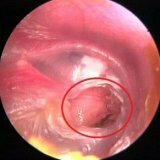

Заболевание эпитимпанит осложненное холестеатомой  Эпитимпанит это одна из форм хронического среднего отита, которая проявляется множественными симптомами и осложнениями. При эпитимпаните происходят значительные разрушения костных тканей, а также результатом заболевания может быть большая потеря слуха по кондуктивному типу. Эпитимпанит чаще всего является причиной внутричерепных осложнений, также может вызывать гнойный лабиринтит, тромбоз вен мозга, поэтому в периоде, когда не существовали антибиотики смертность при эпитимпаните достигала 70-80%.